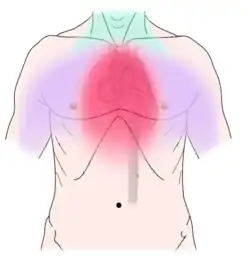

Pulpitis is reversible when the pain is mild to moderate and lasts for a short time after a stimulus (for instance cold); or irreversible when the pain is severe, spontaneous, and lasts a long time after a stimulus. Left untreated, pulpitis may become irreversible, then progress to pulp necrosis (death of the pulp) and apical periodontitis. Abscesses usually cause throbbing pain. The apical abscess usually occurs after pulp necrosis, the pericoronal abscess is usually associated with acute pericoronitis of a lower wisdom tooth, and periodontal abscesses usually represent a complication of chronic periodontitis (gum disease). Less commonly, non-dental conditions can cause toothache, such as maxillary sinusitis, which can cause pain in the upper back teeth, or angina pectoris, which can cause pain in the lower teeth. Correct diagnosis can sometimes be challenging.

Non-dental

Non-dental causes of toothache are much less common as compared with dental causes. In a toothache of neurovascular origin, pain is reported in the teeth in conjunction with a migraine. Local and distant structures (such as ear, brain, carotid artery, or heart) can also refer pain to the teeth.[35]: 80, 81 Other non-dental causes of toothache include myofascial pain (muscle pain) and angina pectoris (which classically refers pain to the lower jaw). Very rarely, toothache can be psychogenic in origin.[10]: 57–58

Non-dental sources of pain often cause multiple teeth to hurt and have an epicenter that is either above or below the jaws. For instance, cardiac pain (which can make the bottom teeth hurt) usually radiates up from the chest and neck, and sinusitis (which can make the back top teeth hurt) is worsened by bending over.[10]: 56, 61 As all of these conditions may mimic toothache, it is possible that dental treatment, such as fillings, root canal treatment, or tooth extraction may be carried out unnecessarily by dentists in an attempt to relieve the individual's pain, and as a result the correct diagnosis is delayed. A hallmark is that there is no obvious dental cause, and signs and symptoms elsewhere in the body may be present. As migraines are typically present for many years, the diagnosis is easier to make. Often the character of the pain is the differentiator between dental and non-dental pain.

Establishing a diagnosis of nondental toothache is initially done by careful questioning about the site, nature, aggravating and relieving factors, and referral of the pain, then ruling out any dental causes. There are no specific treatments for nondental pain (each treatment is directed at the cause of the pain, rather than the toothache itself), but a dentist can assist in offering potential sources of the pain and direct the patient to appropriate care. The most critical nondental source is the radiation of angina pectoris into the lower teeth and the potential need for urgent cardiac care.[10]: 68